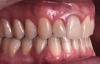

Fig 18. Bite interdigitation to finalize surgical orthodontic correction. After orthodontics, periodontal plastic surgery, bleaching, microabrasion, and restorative dentistry were performed.

Figure 18